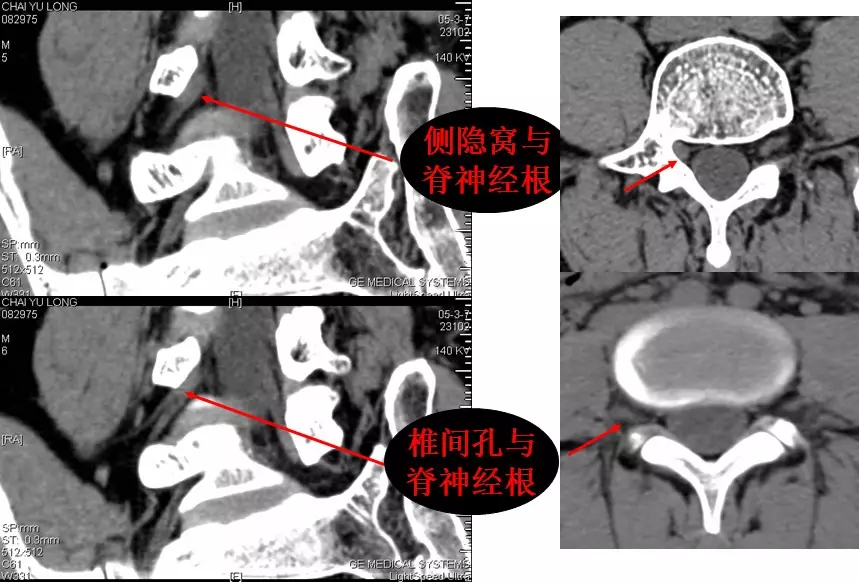

3.椎间孔

位于椎管前外侧,其内的脊神经根呈软组织密度,周围有低密度的脂肪组织环绕。

椎间孔前为椎体,后为椎小关节,上下为椎弓根,内与侧隐窝相连,有脊神经根通过。

侧隐窝:向下外续于椎间孔,有脊神经经过:前壁为椎体后外缘;后壁为上关节突前面与黄韧带;外界为椎弓根。

正常前后径为3-5mm,<3mm侧隐窝狭窄>5mm,肯定不狭窄。